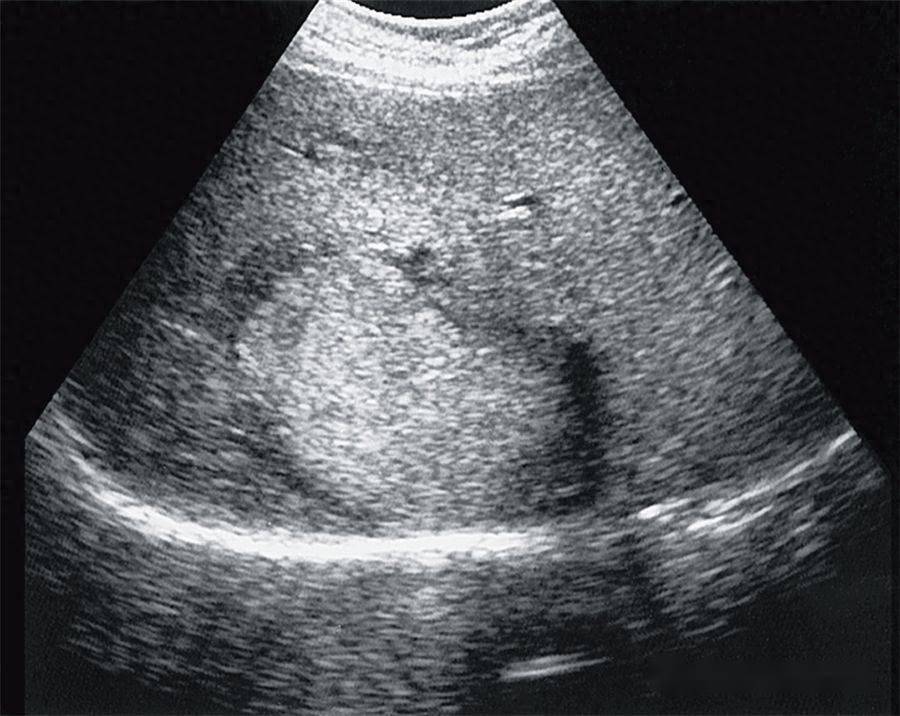

子宫腺肌瘤是怎么回事(子宫腺肌瘤子宫肌瘤傻傻分不清楚)

子宫腺肌瘤和子宫肌瘤,是不是听起来就让我们傻傻分不清楚,好像只是差了一个字,没什么不一样,但是这两个完全就不是一个概念来的。要想知道它们的区别,我们先了解一下女性的一个器官。...